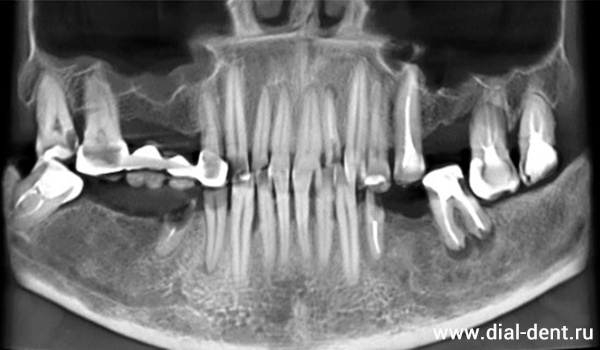

На консультации была выполнена компьютерная томография зубов:

КТ зубов до лечения

Нужно было убрать старый мостовидный протез, удалить несостоятельные зубы, пролечить с микроскопом все, что можно сохранить, установить импланты для замещения отсутствующих зубов и закрыть все зубы коронками для создания правильного по высоте прикуса, чтобы сохранить здоровье суставов.